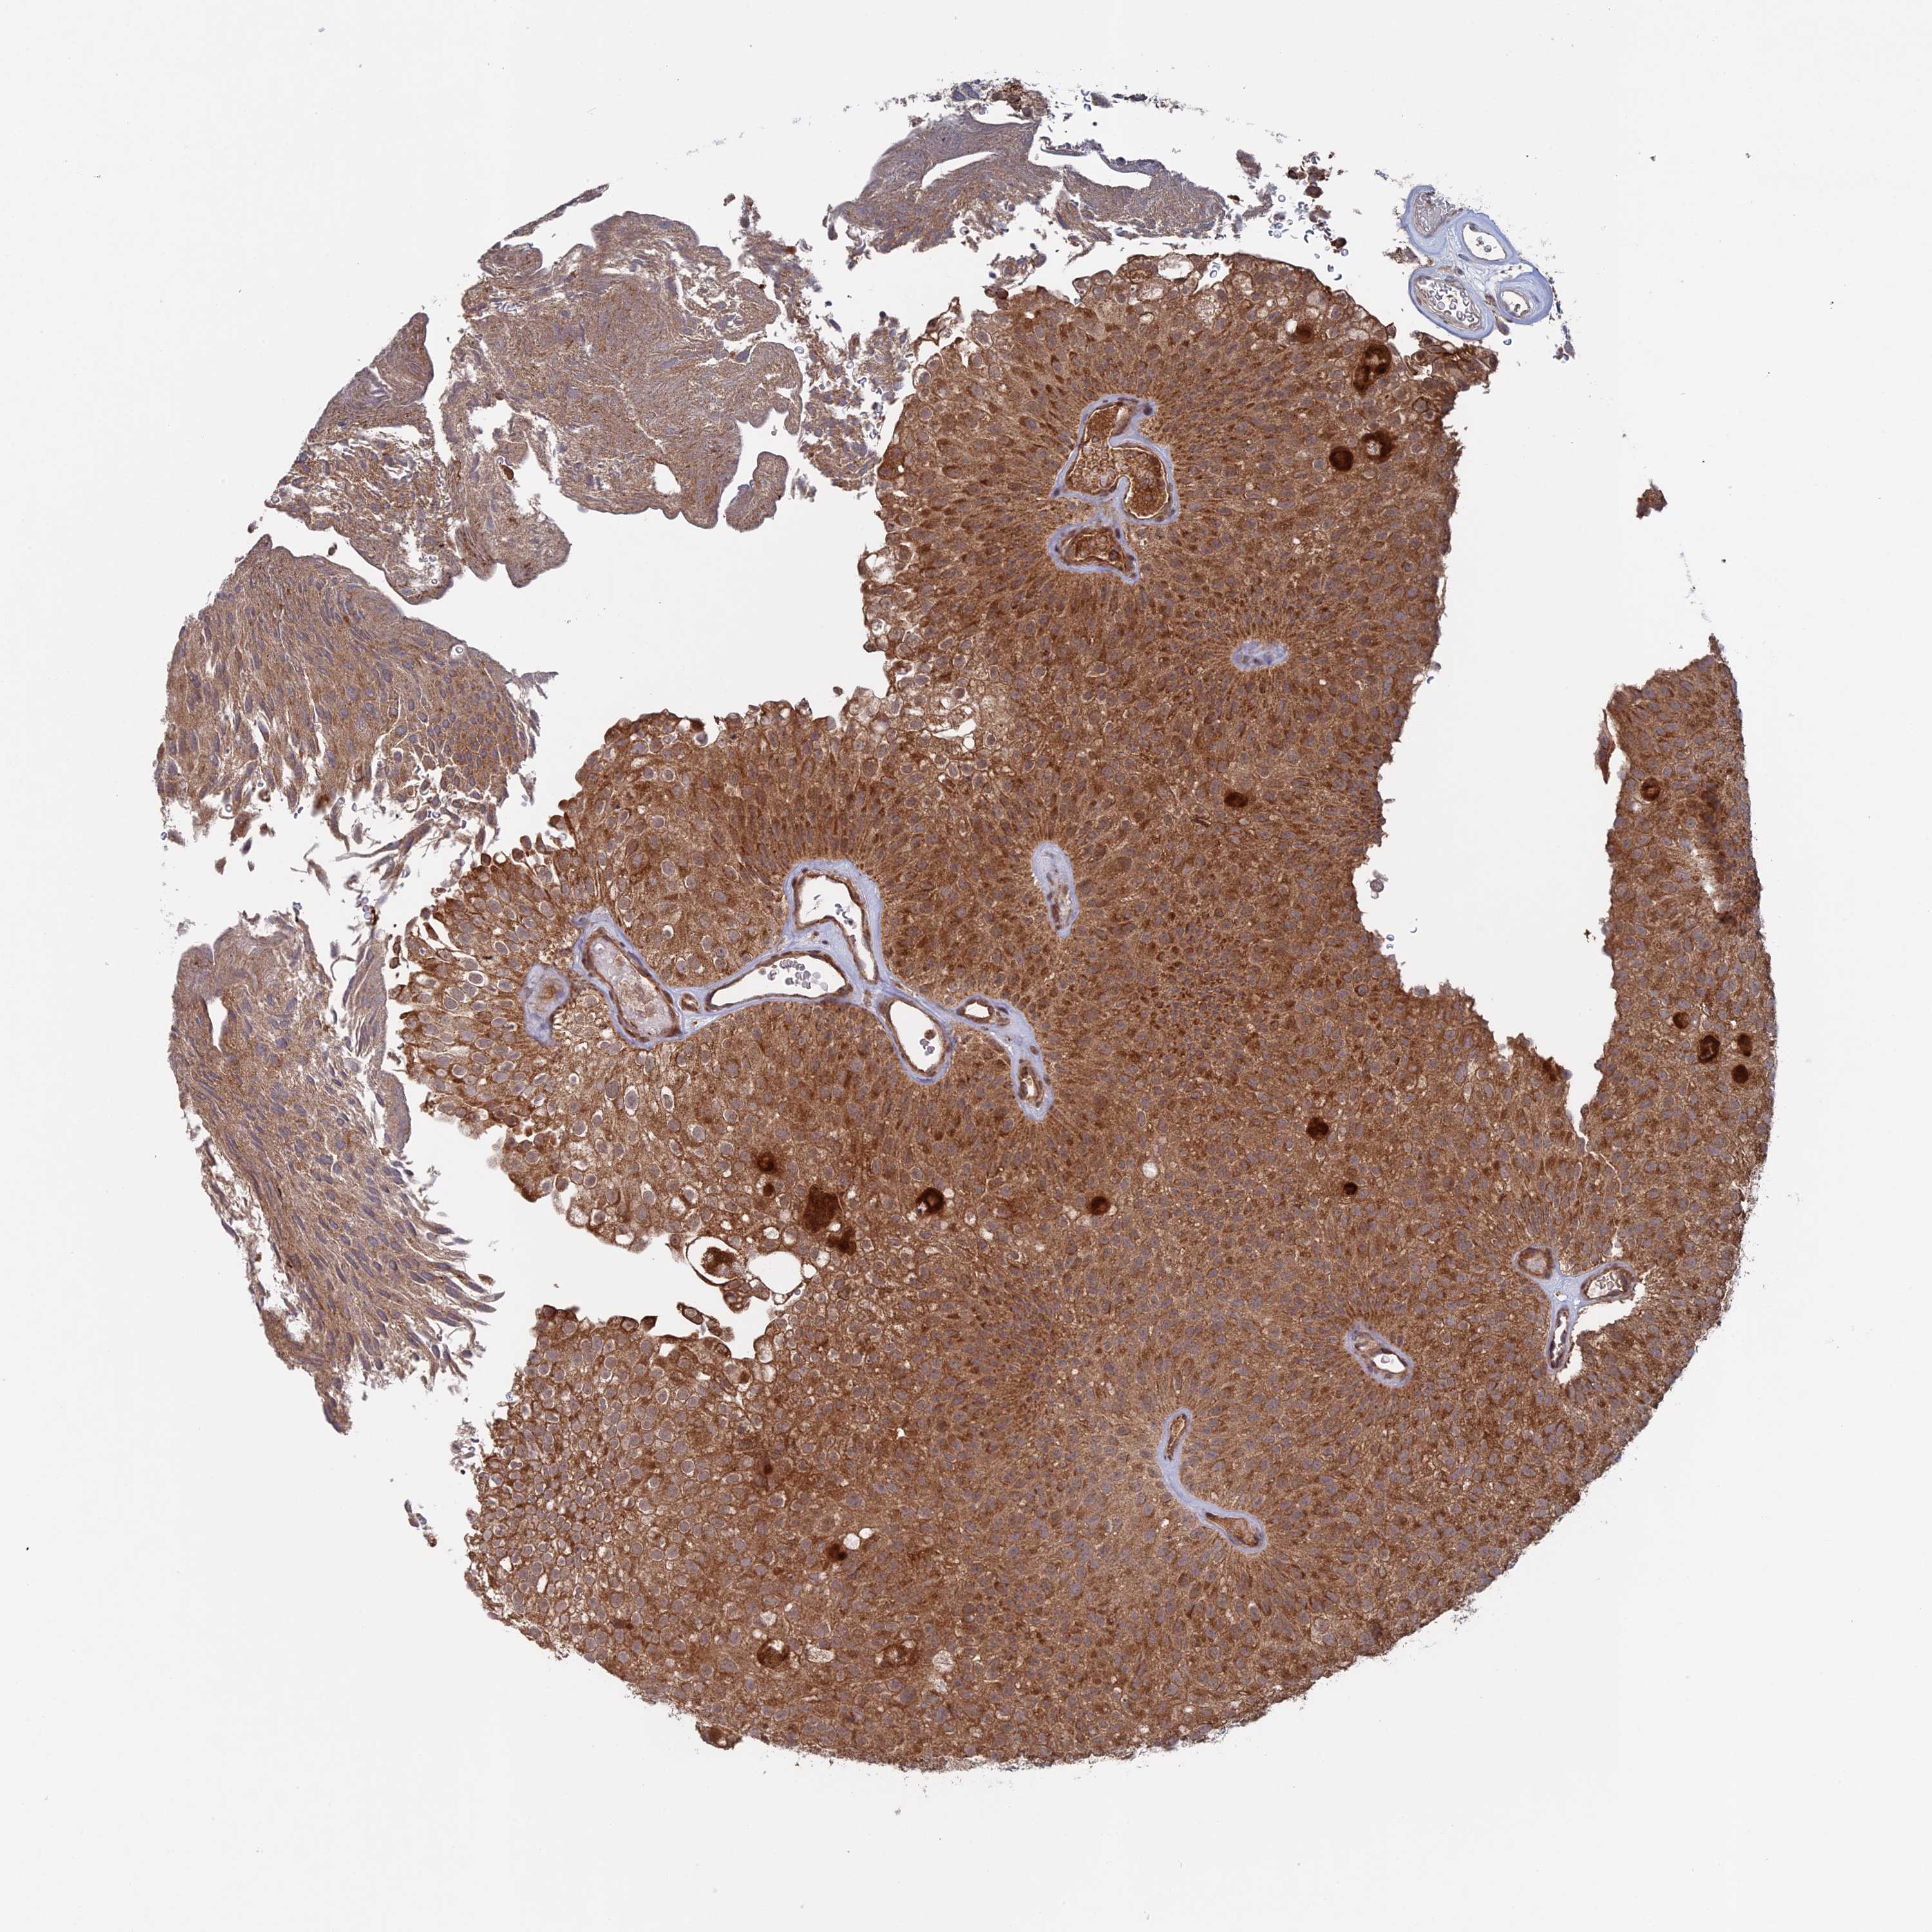

UROTHELIAL CANCER - Protein expressioni

A mouse-over function shows sample information and annotation data. Click on an image to view it in a full screen mode. Samples can be filtered based on level of antibody staining by selecting one or several of the following categories: high, medium, low and not detected. The assay and annotation is described here.

Note that samples used for immunohistochemistry by the Human Protein Atlas do not correspond to samples in the TCGA dataset.

Antibody stainingi

Antibody staining in the annotated cell types in the current human tissue is reported as not detected, low, medium, or high, based on conventional immunohistochemistry profiling in selected tissues. This score is based on the combination of the staining intensity and fraction of stained cells.

Each image is clickable and will lead to virtual microscopy that enables deeper exploration of all samples and also displays staining intensity scores, fraction scores and subcellular localization as well as patient and tissue information for each sample.

Antibody HPA041177

Staining

High

Medium

Low

Not detected

Intensity

Strong

Moderate

Weak

Negative

Quantity

>75%

75%-25%

<25%

None

Location

Nuclear

Cytoplasmic/membranous

Cytoplasmic/membranous,nuclear

Urothelial carcinoma, High grade